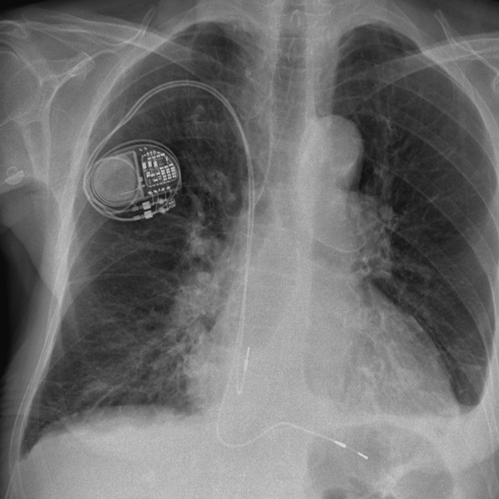

In unseren Katheterlaboren können wir alle verfügbaren ICD´s operativ einsetzen. Die Operation erfolgt ähnlich der Herzschrittmacheroperation. Dabei findet anstelle der normalen Herzschrittmachersonde eine spezielle Defibrillationssonde Anwendung. Das Gerät selbst wird in der Regel unter den großen Brustmuskel in der Nähe des linken Schlüsselbeines eingesetzt.

Bild 1: Zweikammer-ICD mit Elektrode im Vorhof und Defibrillations­sonde (Pfeil) in der rechten Herzkammer